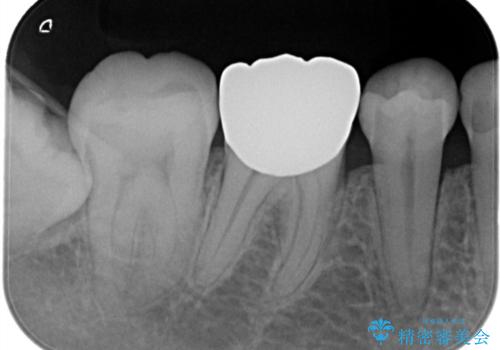

【オールセラミッククラウン】存在感のある銀歯を外したい

- 他院で矯正終了後、保定観察中の患者様が銀歯を白くしたいという主訴で来院されました。

オールセラミッククラウン(st)にて治療を行なっております。

オールセラミッククラウン(st)は

ジルコニアフレームに色調の再現がしやすいポーセレンを焼き付けた構造の被せ物です。